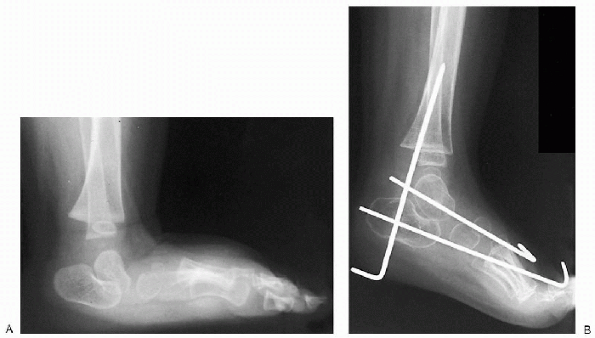

surgery. Details of this procedure are well described by Drennan,

Tachdjian, and Kumar (Fig. 4.3-11). A single

![]() |

Figure 4.3-11 Preoperative (A) and postoperative (B) x-rays.

|